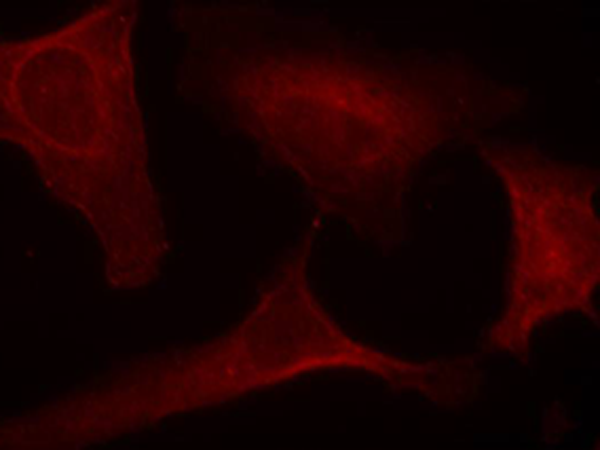

IF Positive control:

Hela cells

IF Recommended dilution

100-200